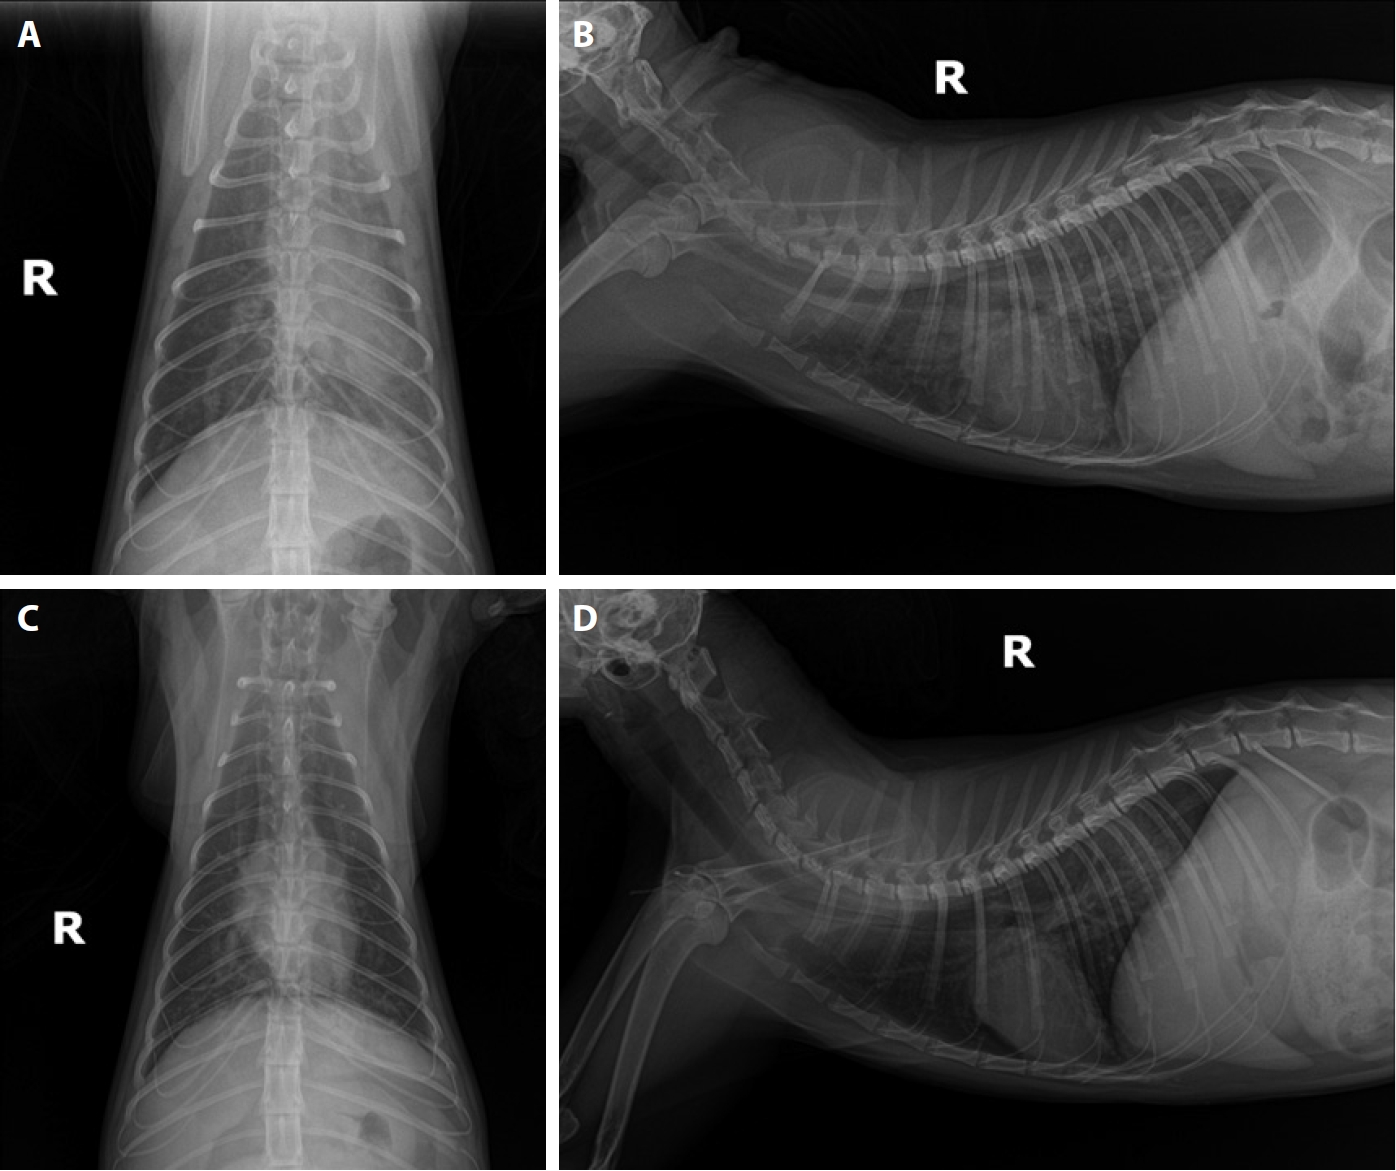

The cat was treated with oxygen supplementation, maintenance fluid therapy, prednisone [1 mg/kg orally (PO) twice daily (BID)], doxycycline (5 mg/kg PO BID), acetylcysteine (10 mg/kg PO BID), pheniramine (1 mg/kg PO BID), and metronidazole (10 mg/kg intravenously BID). Daily thoracic radiographs were obtained to monitor lung condition (

Fig. 1). On hospitalization day 5, thoracic radiographs showed normalization of pulmonary fields. At discharge, prednisone (1 mg/kg PO BID), doxycycline (5 mg/kg PO BID), acetylcysteine (10 mg/kg PO BID), and pheniramine (1 mg/kg PO BID) were prescribed for an additional week to manage HARD [

Fig. 1.Thoracic radiographs of Case 1. Day 1: (A) ventrodorsal view and (B) right lateral view. Pulmonary artery enlargement extending to the right caudal lung lobe is evident in the dorsoventral projection. Additionally, interstitial infiltration is present in the lung field, with multiple fissure lines observed. Day 5: (C) ventrodorsal view and (D) right lateral view. Compared with the findings on Day 1, pulmonary infiltration decreased over the 5-day period.